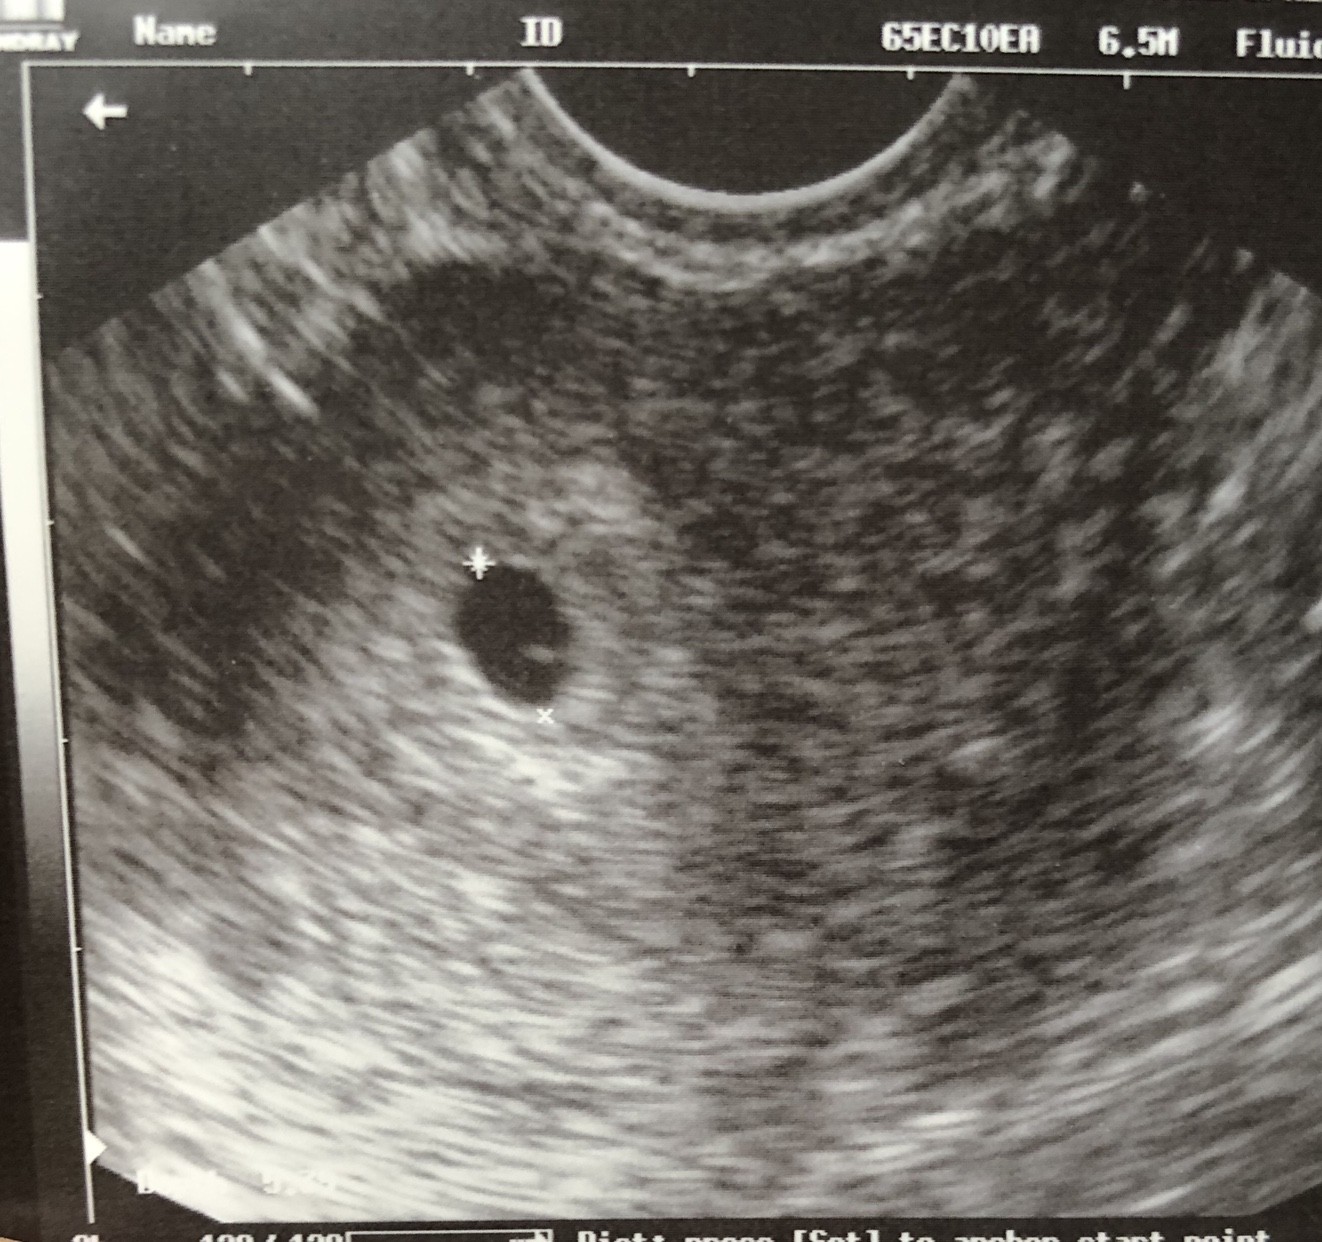

Tak, miałam już jedno za sobą. Póki co był pęcherzyk jeszcze ale wg OM to było dopiero 6+0 tc więc nie zdziwiło mnie to. Ale doktorka powiedziała, że wszystko ok.

[emoji50] nasza mała fasolka z 04.01